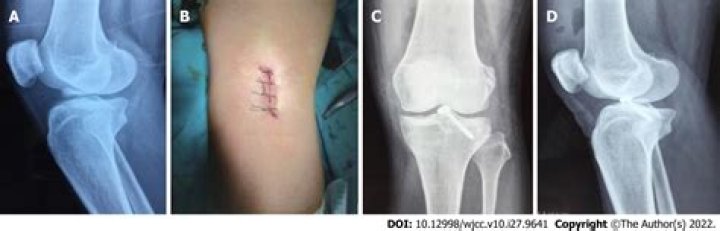

The ideal treatment for avulsion fractures of the inferior pole of the patella has not yet been identified. The options include internal fixation of the pole fragment and resection of the avulsed fragment along with the repair of patellar ligament to the patella.

You may need surgery if the bone fragment is large and widely separated from the rest of the bone. Surgery may also be done if a tendon or ligament is badly detached. You can return to sports or other physical activities after about 6 weeks to 6 months.